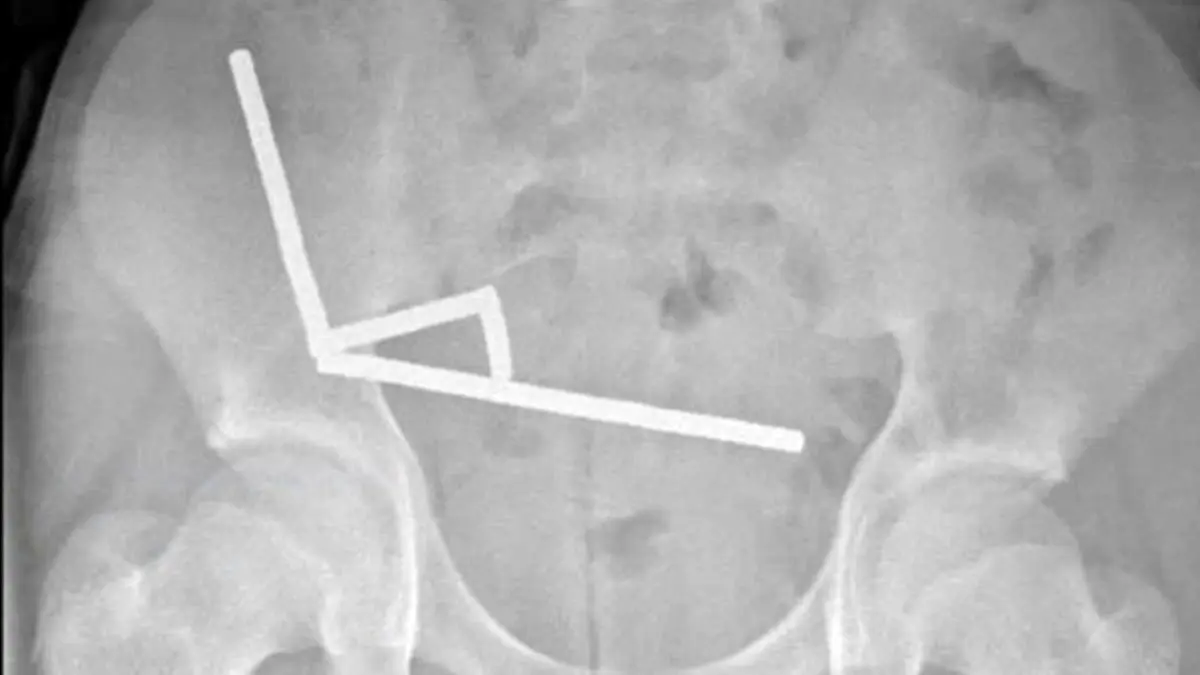

نوجوان ۱۳ سالهای در نیوزیلند پس از بلعیدن نزدیک به ۲۰۰ آهنربای قوی، دچار پارگی و انسداد روده شد و پزشکان ناچار شدند بخشی از روده او را خارج کنند؛ حادثهای تکاندهنده که بار دیگر خطر «آهنرباهای اسباببازی» را یادآور شد.